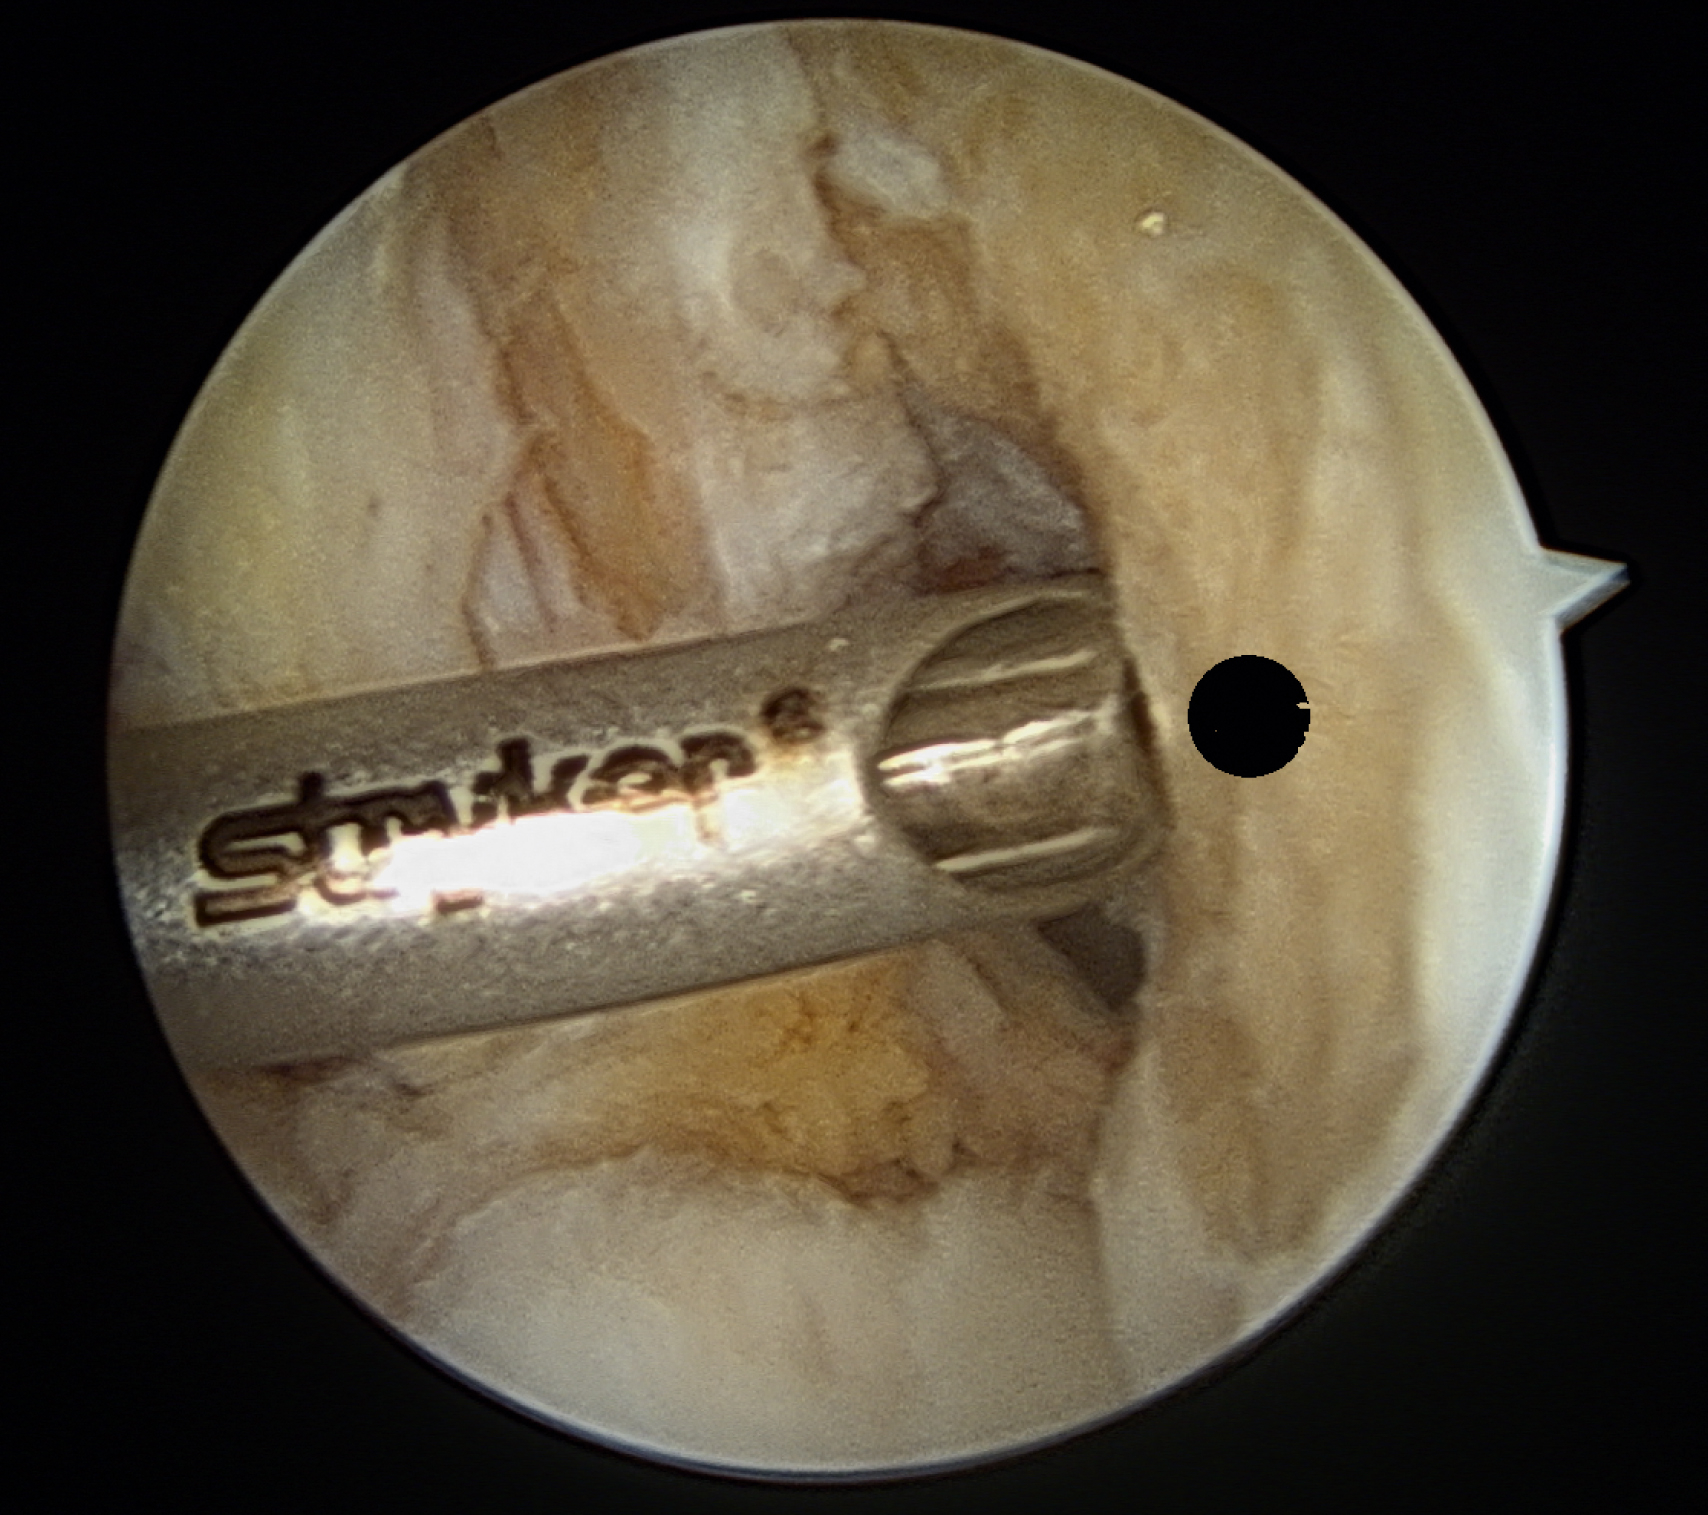

Tunnel Creation

A minimal notchplasty (2 mm) of the lateral wall will facilitate visualization, and a débridement of soft tissue from the lateral wall will also help locate the ACL center. After identifying the point for the femoral tunnel, an awl is used through the medial portal to create a pilot hole for reaming ( Fig. 49.5 ). It is helpful to verify the position of the pilot hole by visualization through the medial portal. The pilot hole should be approximately 8.5 mm (range 8.0–9.5 mm) up the lateral wall and slightly deep to the midpoint between the front and back of the notch ( Fig. 49.6 ).